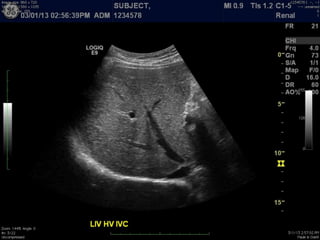

Modalities

B-mode, 2D imaging

A Primer ofDiagnostic Ultrasonic Imaging Modalities B-mode, 2D imaging